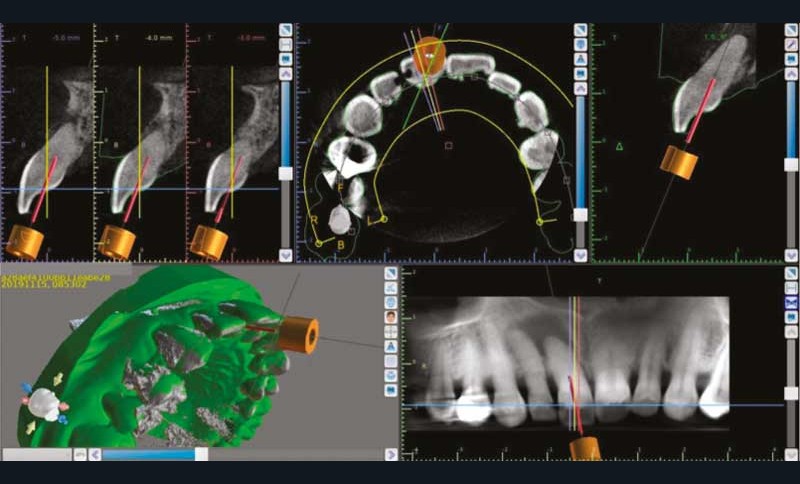

Les technologies de CFAO (Conception et Fabrication Assistées par ordinateur) couplées aux images issues du CBCT ont étendu l’exercice de l’endodontie au champ de la chirurgie guidée [3]. La conception de guides endodontiques par impression 3D est désormais possible à partir d’une empreinte numérique et d’un examen radiographique tridimensionnel. La planification numérique permet de simplifier des traitements difficiles (canaux calcifiés, suites de trauma, dens in dente) [4] (fig. 2). Par ailleurs, l’endodontie guidée répond aux exigences d’économie tissulaire, réduit le temps opératoire et constitue une approche sécuritaire, limitant les risques liés à la trépanation lors de l’aménagement des voies d’accès [5, 6].